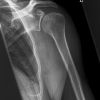

Schulter a.-p. (chirurgisch)

Technik

• FDA: 1,15 m

• Ausgangsformat: 24/30 hoch

• mit Raster

Fraktur, Luxation, Osteosynthesematerial

sitzend/ stehend aufrecht am Rasterwandstativ

nicht aufzunehmende Seite um 45° anheben

Hand in Supination, Arm leicht abspreizend

Querstrahl: ergibt sich durch 2 QF Licht über Schulter-Haut-Grenze

Längsstrahl: über Gelenkspalt

evtl. Tiefenblende anpassen

Gelenkfläche der Scapulapfanne (Glenoidal-Gelenk) soll strichförmig abgebildet sein, der Humerus soll frei projiziert werden. Die Aufnahme kann mit der Rockwood-Aufnahme kombiniert werden (Röhrenkippung). evtl. Schulterfilter verwenden.

- vollständige überlagerungsfreie Darstellung des Humeruskopfes und des Gelenkes